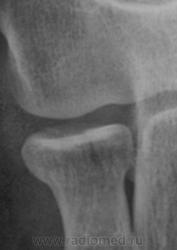

Рентгенограмма в прямой проекции.

Фрагменты с увеличением.

Предположу продольный перелом головки луча с допустимым смещением.

Красивое наблюдение - нечастая локализация...